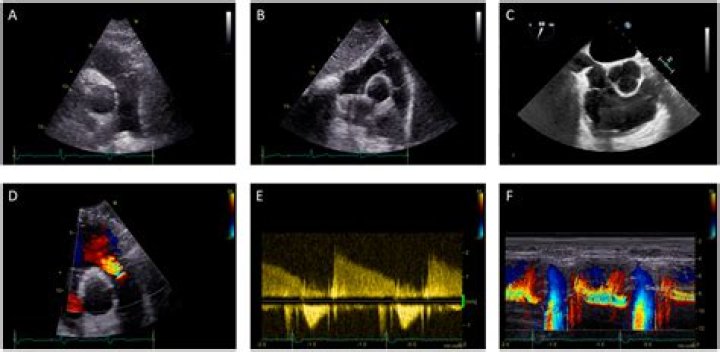

Which Artery is Blocked? An Echo Challenge